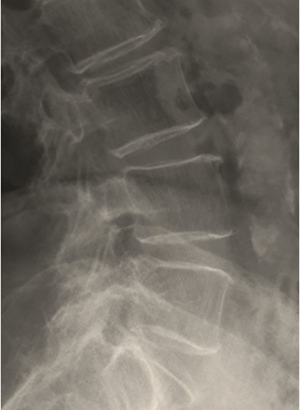

Conventional radiography

Findings suggestive of osteoporosis are frequently encountered on radiographs and it is extremely important for the radiologist to be aware of them. The main radiographic features of osteoporosis are: (I) increased bone radiolucency; (II) cortical thinning; (III) changes in the trabecular pattern (38,39). Increased bone radiolucency (I) results from the progressive decline in BMC and the concomitant impoverishment of the trabecular microarchitecture, resembling the appearance of an over-exposed radiograph. However, this feature is detectable only in the advanced stages of the disease, when the amount of bone loss reaches at least 30% (39). Cortical thinning (II) results from the reabsorption of the periosteal, intracortical and endosteal layers. The resorption process is very active in the endosteum because of its rich blood supply, resulting in a gradual widening of BM space. In the vertebral bodies, this feature together with the concomitant increase in bone radiolucency is responsible for the typical “picture frame” appearance, also known as ‘‘ghost vertebra’’ (Figure 1) (38,39). In the early-stages of osteoporosis, a scalloping in the inner margin of the cortex, known as “endosteal scalloping”, can be seen, but this finding is non-specific and can be found also in pathologic conditions characterized by rapid bone turn-over like hyperparathyroidism, renal osteodystrophy or reflex sympathetic dystrophy syndrome. Lastly, the alteration in trabecular pattern (III) is caused by the fact that trabeculae, which are more abundant in the axial skeleton and at the ends of long bones, offer a greater surface area for resorption processes and respond faster to metabolic changes than cortical bone (38,39). Early on, secondary trabeculae, which are not primarily involved in weight bearing, are lost first, while the primary trabeculae become more prominent and will disappear only at a later stage. Using these specific and predictable sequence of resorptive processes, some authors developed semi-quantitative indexes for the diagnosis and grading of osteoporosis. Among these indexes, those proposed by Singh et al. considering the proximal femur and by Jhamaria at al. considering the calcaneus were perhaps the most widely used ones in the past (40-42). However, these indexes suffer from a great inter-observer variation and the quality of the radiographs itself and the superimposition of soft tissues (with particular regards to the Singh index) can also affect the results. An extended description of these indexes is beyond the purpose of this article, and for a more comprehensive discussion, the interested reader is referred to the referenced publications (38,40-42).